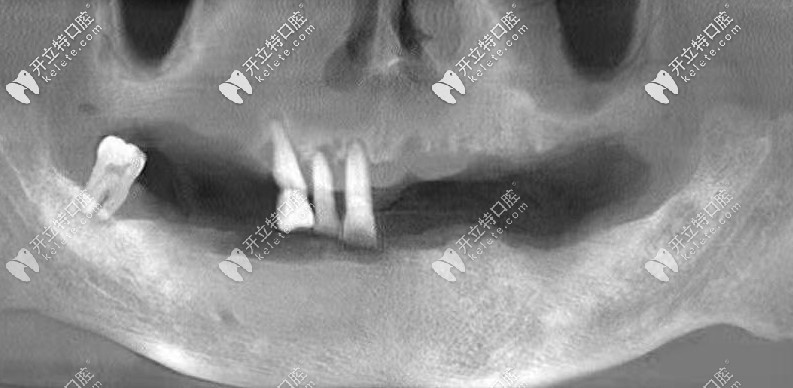

爺爺做全口種植牙后拍的CT↓↓↓

種牙前爺爺?shù)目谇粻顩r↓↓↓

經(jīng)過檢查發(fā)現(xiàn),爺爺牙槽骨萎縮比較厲害,如果選擇常規(guī)種牙的話,是需要植骨粉骨膜的,花費(fèi)大不少,而且相對(duì)比較痛苦。

所以,醫(yī)生推薦了allon6種植牙技術(shù),這個(gè)不可不用植骨粉骨膜,而且當(dāng)天種牙,戴上臨時(shí)牙冠,回家就可以吃東西了。